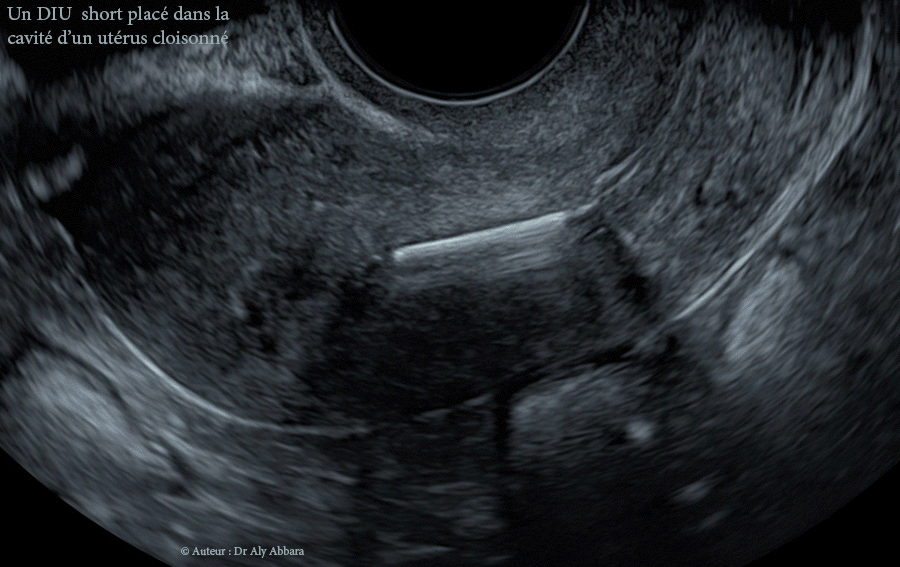

Positionnement d'un DIU au cuivre dans la cavité d'un utérus malformé, cloisonné

• Images échographiques montrant, sur une coupe frontale (3D) puis une coupe sagittale médiane (2D), le positionnement d'un DIU(Cu) short (en T) dans la cavité utérine d'un utérus malformé cloisonné partiel corporéal (U2a = utérus extérieurement normal avec un septum fundique interne médiane supérieur à 50 % de l'épaisseur de la paroi utérine).

Il s'agit d'une cloison utérine corporéale verticale médiane méconnue au moment de la pose de ce DIU (stérilet) chez une femme âgée de 25 ans, nulligeste.

• Ces images expliquent le positionnement bas du DIU dans la moitié inférieure de la cavité du corps utérin tout en laissant les deux cornes utérines (formées par la présence de la cloison) hors contact avec les différentes composantes du DIU (la tige verticale cuivrée et les deux bras horizontaux).

• Cette occupation partielle de la cavité utérine par le DIU peut comporter probablement le risque de réduire son effet contraceptif par son manque de contact avec l'endomètre et par une diffusion insuffisante du cuivre dans la cavité utérine.